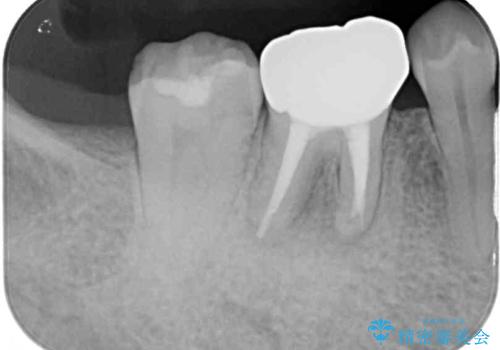

歯肉には膿の出口が見られ、レントゲン写真からは歯根周辺に病変が認められたため、まずは根管治療を行い、その後フルジルコニアクラウンにて補綴することとしました。

フルジルコニアクラウンを装着してからは、気になっていた金属の縁がなくなり、また、咬み合わせも非常に安定しており、患者様には大変満足していただきました。